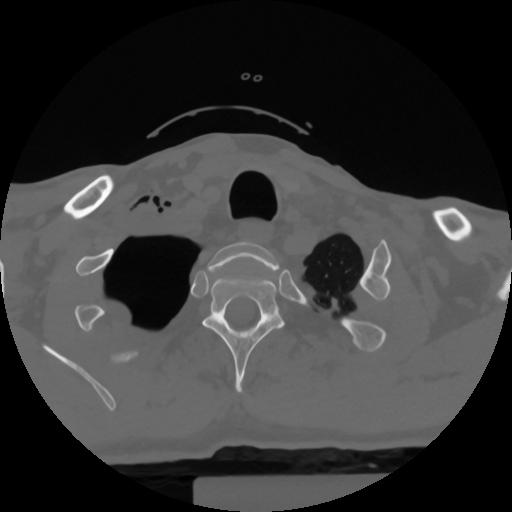

12 P.BLANDAS,,Vol,0.5,P.BLANDAS,,